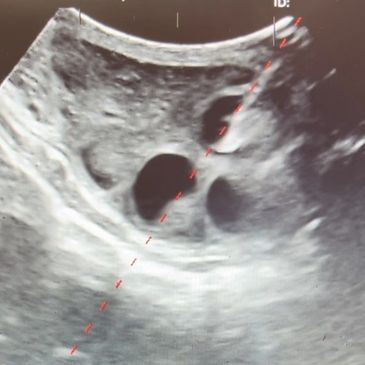

An OPU probe contains an ultrasound and needle guide, so that the ovary can be visualized then stabilized for aspiration.

A needle is guided through the OPU probe and follicles on the ovary are individually penetrated. The follicle contains both follicular fluid and an oocyte. Similar to embryos, the oocyte is too small to see with a naked eye.